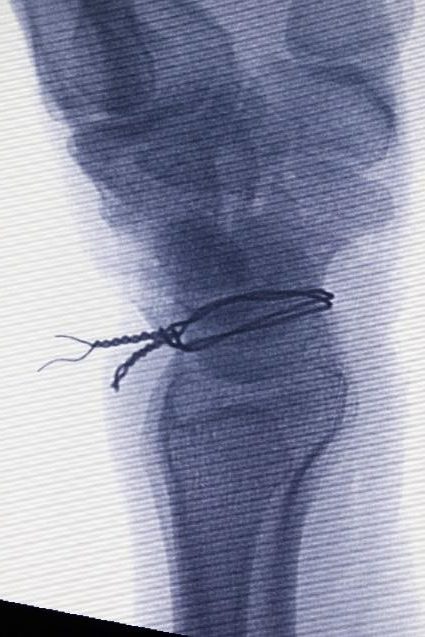

Aşağıda gösterildiği gibi, instabiliteyi sabitlemek için volar ve dorsal ligamanın skafolunatını tendon grefti ile yeniden yapılandırmak genellikle tercih edilen prosedürdür.